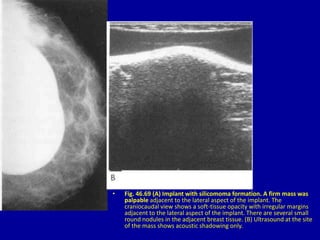

• Fig. 46.69 (A) Implant with silicomoma formation. A firm mass was

palpable adjacent to the lateral aspect of the implant. The

craniocaudal view shows a soft-tissue opacity with irregular margins

adjacent to the lateral aspect of the implant. There are several small

round nodules in the adjacent breast tissue. (B) Ultrasound at the site

of the mass shows acoustic shadowing only.

• Fig. 46.69(A) Implant with silicomoma formation. A firm mass was palpable adjacent to the lateral aspect of the implant. The craniocaudal view shows a soft-tissue opacity with irregular margins adjacent to the lateral aspect of the implant. There are several small round nodules in the adjacent breast tissue. (B) Ultrasound at the site of the mass shows acoustic shadowing only.